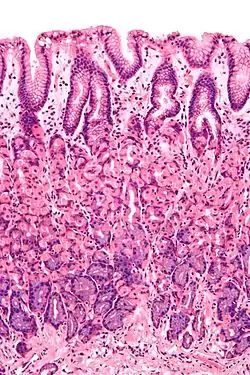

Simple columnar epithelium is a single layer of columnar epithelial cells which are tall and slender with oval-shaped nuclei located in the basal region, attached to the basement membrane. In humans, simple columnar epithelium lines most organs of the digestive tract including the stomach, and intestines. Simple columnar epithelium also lines the uterus.

The shape of the simple columnar epithelium cells are tall and narrow giving a column like appearance. the apical surfaces of the tissue face the lumen of organs while the basal side faces the basement membrane.[1] The nuclei are located closer along the basal side of the cell.[1]

Absorptive columnar epithelium is characterized as having a striated border on its apical side, this border is made up of non-motile microvilli allowing for increase surface area for absorption.[1] These are known as non-ciliated columnar epithelium. Non-ciliated simple columnar epithelium is made up of glandular goblet cells which secrete mucin to form mucus.[1] The rest of the cell is made up of cytoplasm with membrane bound secretory granules which secrete the mucin, and are found towards the apical surface of the cell.[1]

Vertical section of a villus from the dog's small intestine. X 80. (Simple columnar epithelium labelled at right, third from the top.)

Transverse section of a villus, from the human intestine. X 350.

a. Basement membrane, here somewhat shrunken away from the epithelium.

b. Lacteal.

c. Columnar epithelium.

d. Its striated border.

e. Goblet cells.

f. Leucocytes in epithelium.

f’. Leucocytes below epithelium.

g. Blood vessels.

h. Muscle cells cut across.